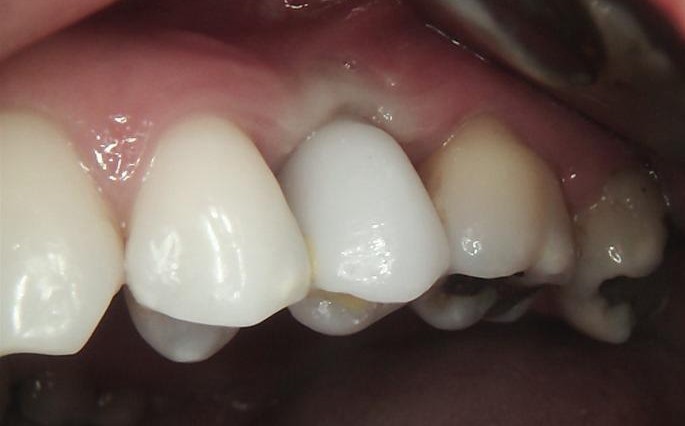

FINAL

After successful osseointegration, the definitive restoration was delivered using a Ti-base-supported crown, held by Dr Carmy.

Final radiographic evaluation confirmed proper implant positioning and bone stability.

The treatment resulted in a functional, stable, and esthetically harmonious restoration fully integrated with the adjacent dentition.